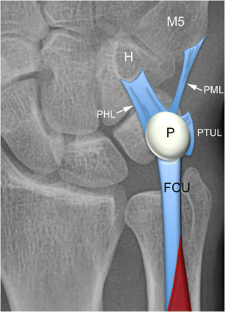

Fig. 4